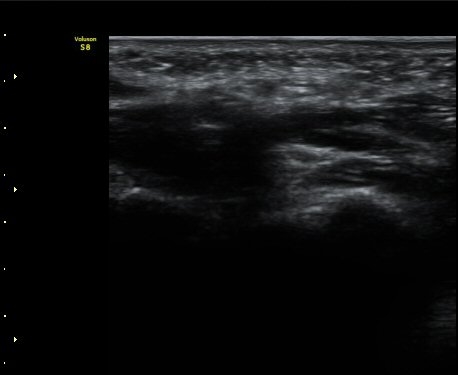

ÃÊÀ½ÆÄ °Ë»ç

¼Õ¹Ù´Ú ºÎÀ§ Á¤Á߽Űæ Á¾´Ü¸é°Ë»ç¿¡¼­ Á¤Áß½É°æ ½ÉºÎ¿¡ µÕ±Ù Àú¿¡ÄÚ Á¾±«°¡ °üÂûµÈ´Ù(»çÁø 1).

Äá¾Ë»À(pisiform) ºÎÀ§ ô°ñ½Å°æ Ⱦ´Ü¸é°Ë»ç¿¡¼­ Á¤Á߽Űæ°ú ô°ñ½Å°æÀÌ Á¤»óÀûÀÎ ¸ð½ÀÀ¸·Î

°üÂûµÈ´Ù(»çÁø 2).